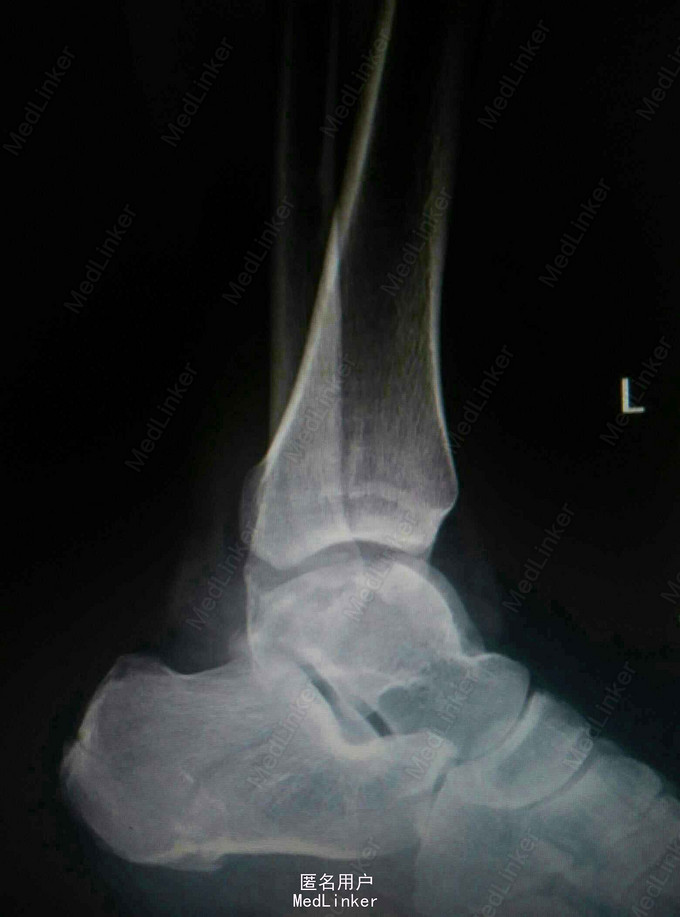

患者,男,27岁,高处坠落致左踝部肿痛,活动受限

完善X线片及CT扫描检查